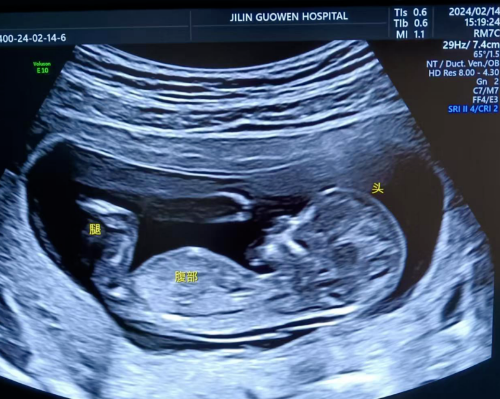

品質(zhì)國(guó)文 | 寶媽看過來!胎兒NT彩超免費(fèi)檢查

寶媽看過來!胎兒NT彩超免費(fèi)檢查長(zhǎng)春國(guó)文醫(yī)院支持國(guó)家優(yōu)生優(yōu)育政策,回饋寶媽,NT彩超檢查免費(fèi)。那么,什么是NT檢查呢? 閱讀量:1417